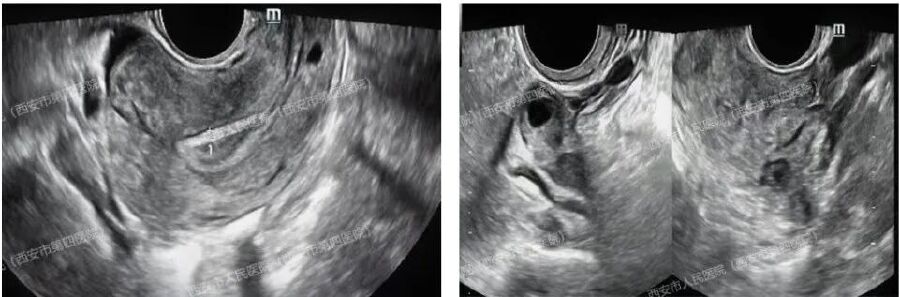

左圖腔內超聲顯示宮腔內未見孕囊

右圖顯示右側卵巢小囊腫